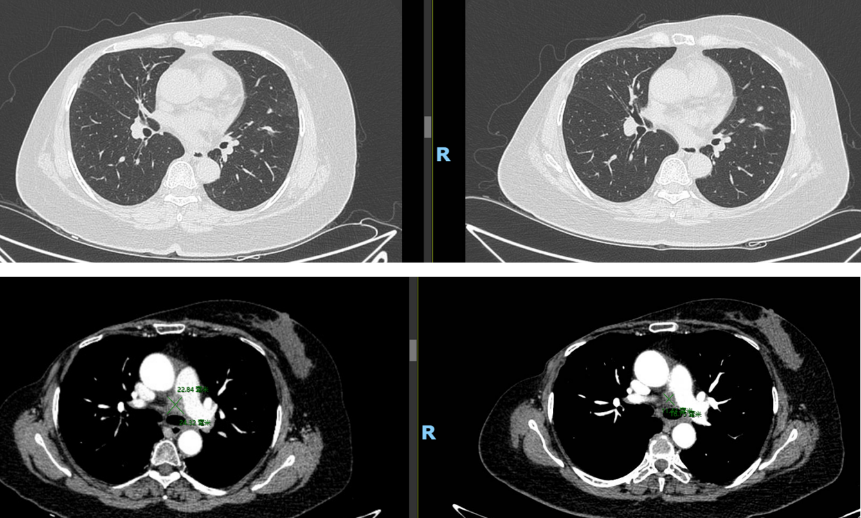

至2022年12月,患者CEA及CA15-3持续升高;2023年6月进一步检查提示疾病全面复发,DFS约60个月。PET/CT显示左肺上叶下舌段结节、区域多发肿大淋巴结以及胸腰椎多发骨质破坏,并伴糖代谢增高,提示肺、淋巴结及骨转移。

在一线阶段,患者于2023年6月接受哌柏西利联合氟维司群,并联合双膦酸盐类治疗。对于HR+/HER2-晚期乳腺癌而言,这一方案符合当下标准治疗思路。然而,至2024年6月复评时,患者出现纵隔淋巴结进展及骨转移进展,虽然肺部病灶达到PR,但总体仍判断为一线进展。这意味着患者并未获得与经典研究中相符的持久一线控制,也提示其肿瘤可能存在较强的早期耐药驱动。

治疗一周期后,影像学显示病灶明显缩小。在后续维持治疗中,靶病灶达到完全缓解(CR),非靶病灶状态为non-CR/non-PD。患者维持深度缓解状态,二线PFS高达17个月。